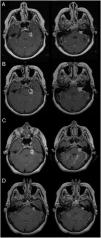

ResultsThe mean age at treatment was 53 years, 56% were women. Ninety-eight percent of the patients had hearing loss, 71% with grade III according to the Gardner–Robertson Classification. The mean volume at treatment was 2.92cc and the mean follow-up, 40.95 months. The overall therapeutic success was 90%, reaching 100% at 12 and 24 months, and 86% after 36 months of follow-up. The radiological result was significantly related to the initial tumour volume (p<0.037). In 20 patients there was evidence of transient tumour growth compatible with pseudoprogression. Acute complications were present in 37.5%, and transitory complications in 50%. Chronic complications were found in 20%, with 84% being permanent. The rate of acute complications was lower in patients with regression (p<0.016). Chronic complications were more frequent in the 41–60 year old age group (p<0.040).

ConclusionsIn our study, the overall tumour control was in accordance with other published series. The radiological result significantly related to the tumour volume at the commencement of treatment. The rate of acute complications was lower in patients with regression.